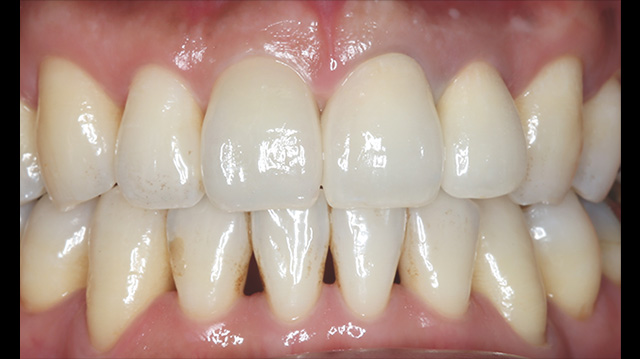

| 年代・性別 | 50代 男性 |

|---|---|

| 主訴 | 前歯を綺麗にしたい |

| 治療回数 | 3回 |

| 治療期間 | 約1ヶ月 |

| 費用 | 仮歯 5,500円 ジルコニアクラウン 176,000円 |